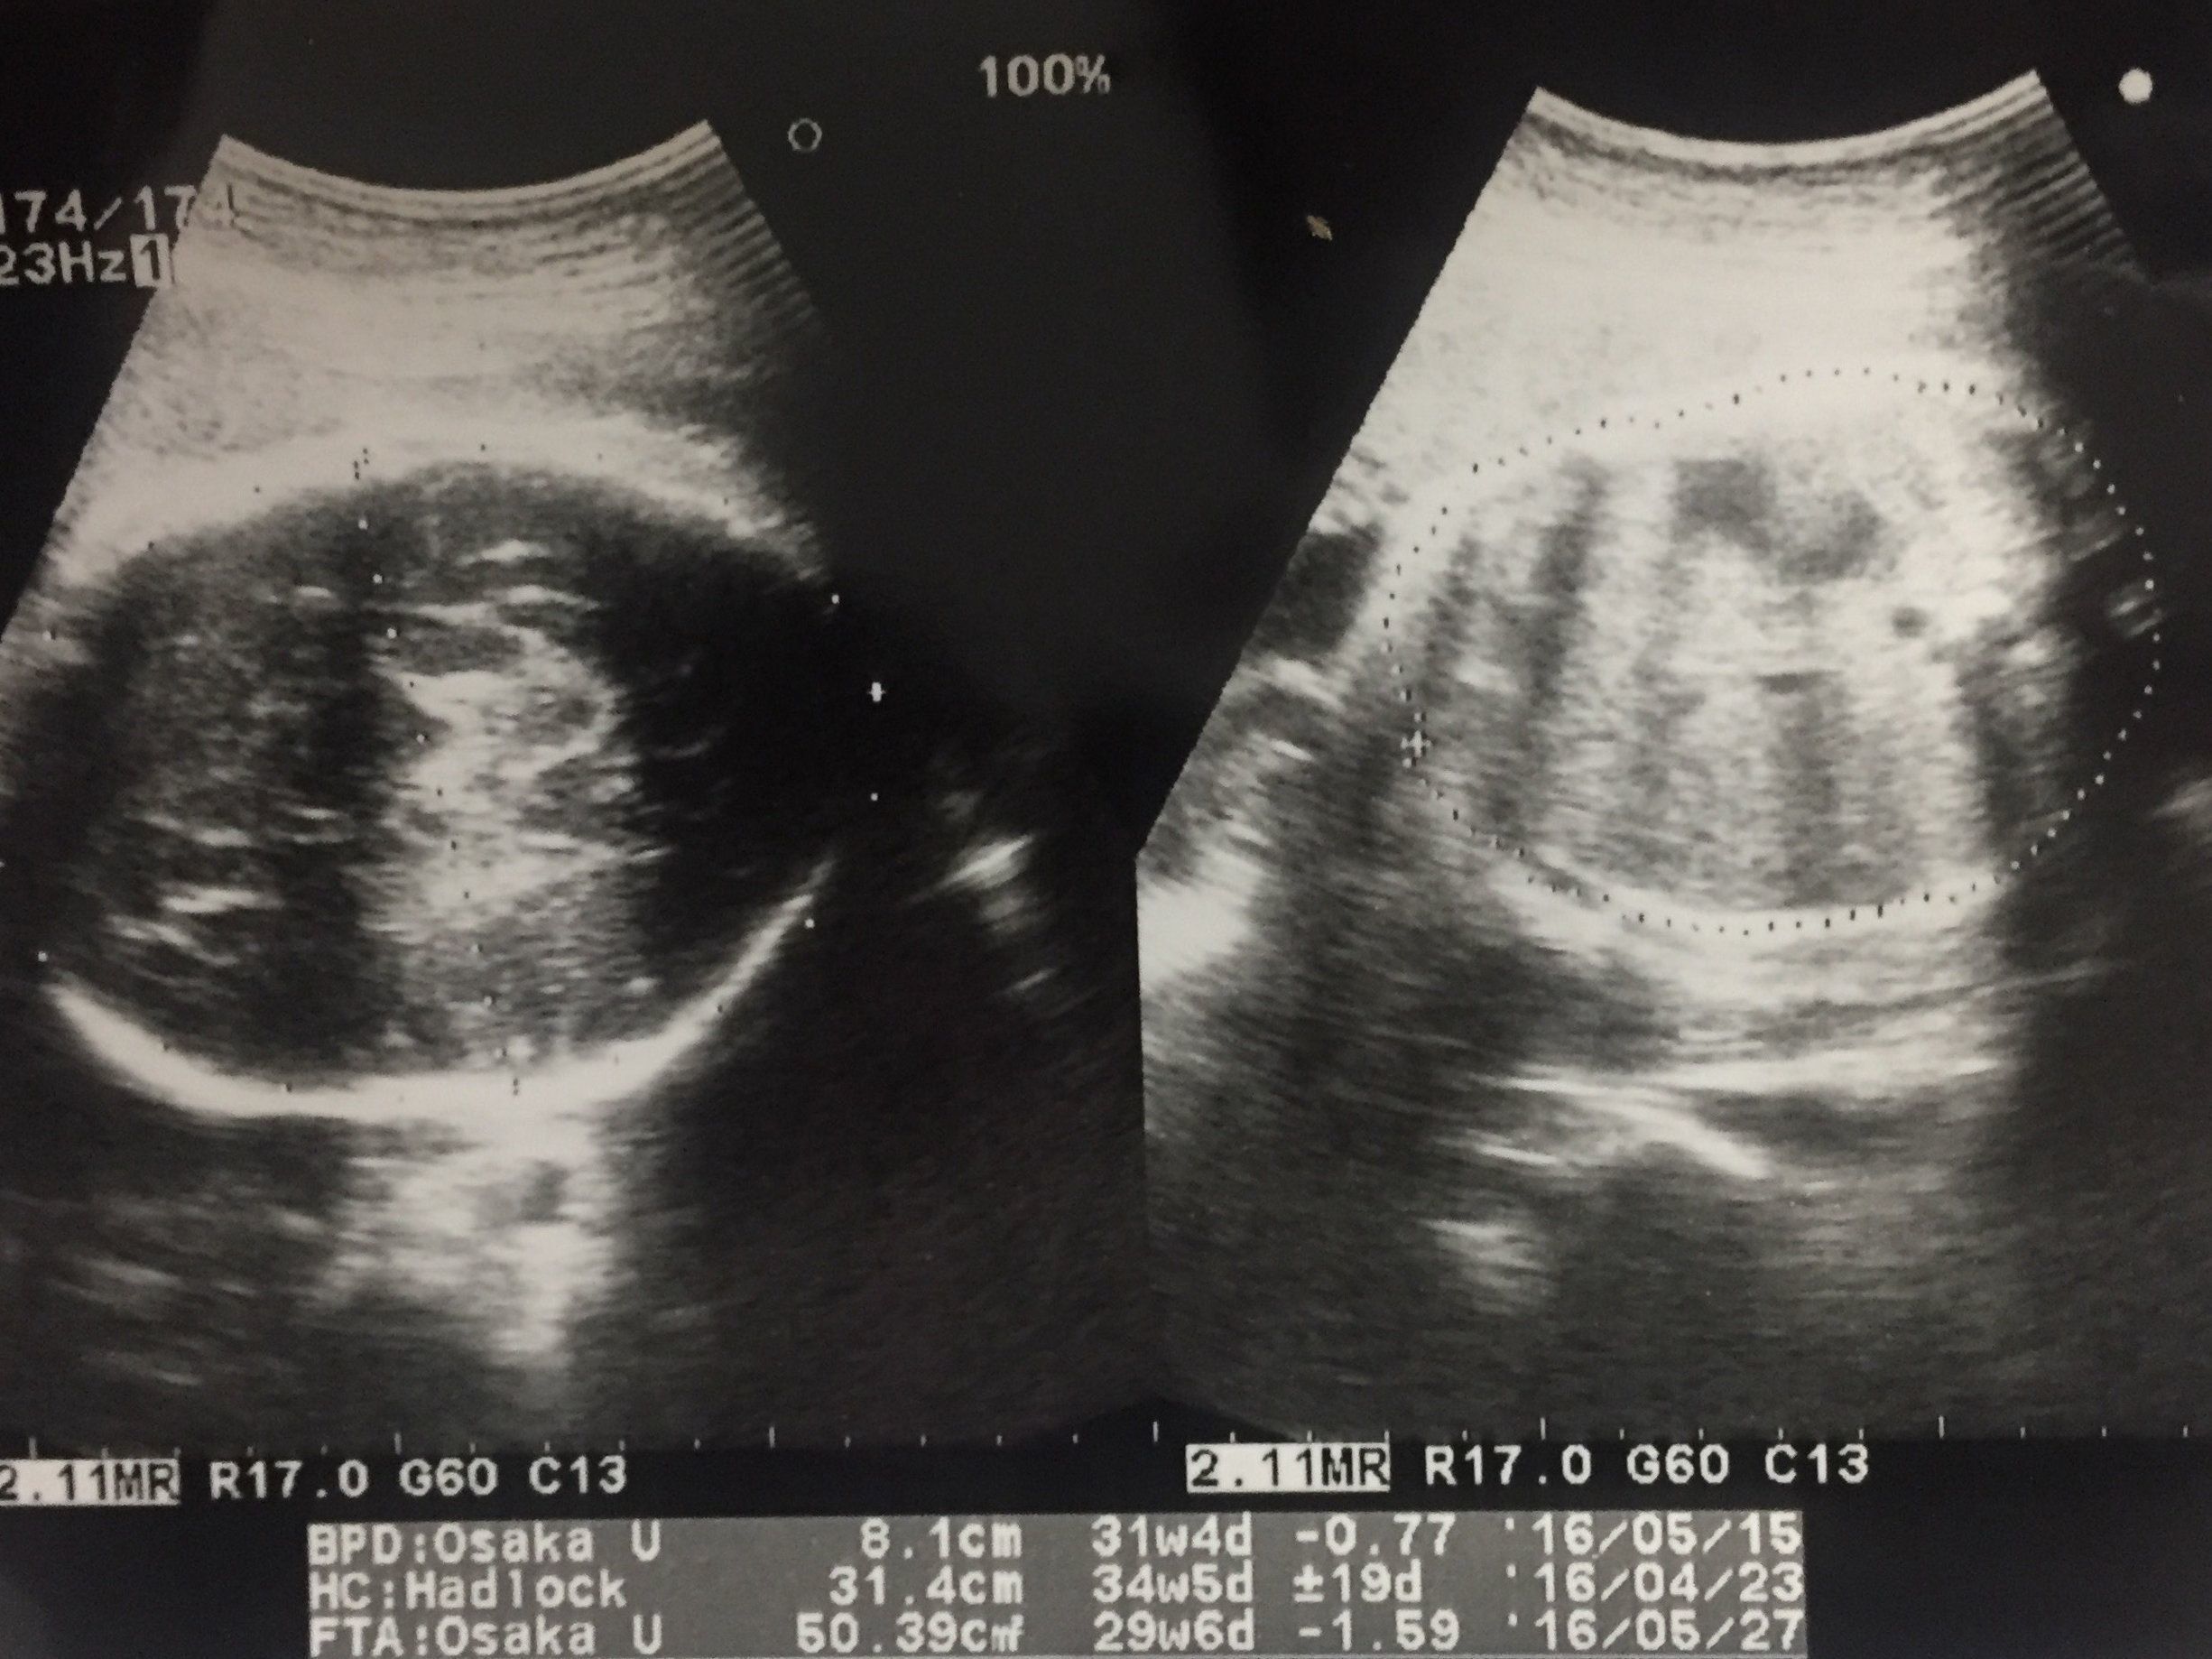

妊娠29週目 逆子で帝王切開の可能性も視野に

赤ちゃんの頭を上から撮影したものです。妊娠20週あたりから健診の度に「逆子だけど、そのうち回転するかもしれない」と言われてきました。それほど気にしていなかったのですが、そのまま妊娠後期に入ったので「このままだと帝王切開になるのだろうか」と考え始めました。

普通分娩の強い希望があったわけでもなかったので、冷静に帝王切開について調べて心の準備をしていました。

この写真は、赤ちゃんを頭上から撮影したものです。赤ちゃんが元気で順調に育っている様子をエコーで確認できたので、ひと安心。